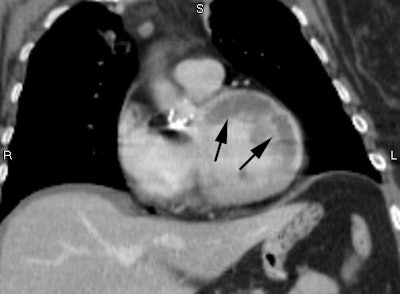

CT:

On dynamic imaging, an acute area of myocardial infarction will demonstrate decreased contrast enhancement.

.Massive acute MI: Contrast CT demonstrates a massive acute MI with extensive areas of decreased enhancement involving the anterior, lateral, and septal walls (black arrows). Inferior wall is enhancing normally. Note bright epicardial enhancement in the infarcted regions (white arrows).